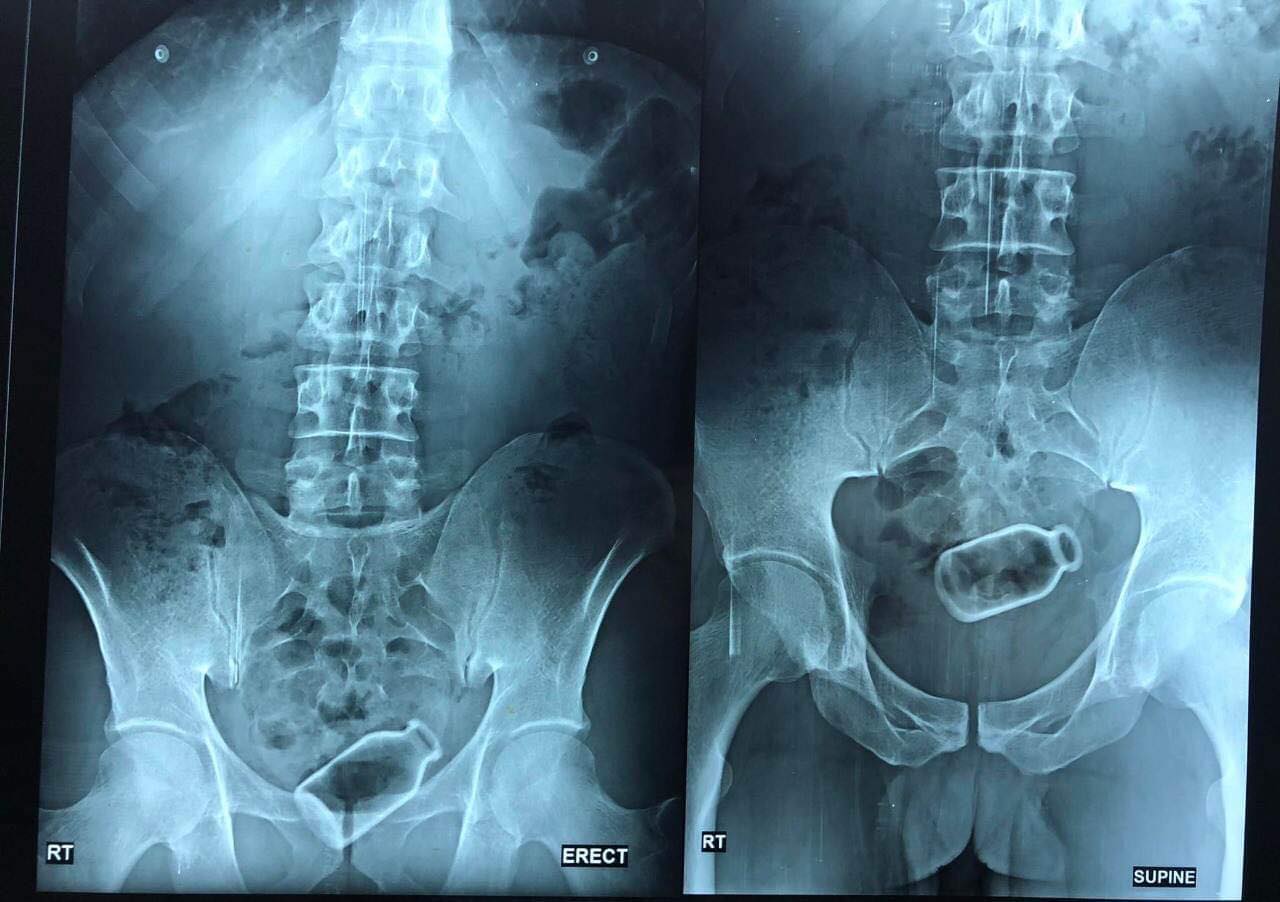

تمكن فريق طبي بمستشفى خاصة في المنصورة، محافظة الدقهلية، اليوم، من استخراج زجاجة دواء كبيرة الحجم من بطن شاب من محافظة المنوفية باستخدام المنظار الطبي، بعد معاناة صحية عاشها الشاب على مدار أسبوعين، نظرا لأنه لديه مشاكل نفسية، وعندما أصيب بالإمساك استخدم الزجاجة للتخلص من الإمساك إلا أنها دخلت إلى القولون وابتعدت حتى أنها لا يمكن إخراجها إلا بتدخل طبي.

وقالت الدكتورة أسماء جميل، مدرس واستشاري الكبد والجهاز الهضمي والمناظير جامعة المنصورة، إن أسرة الشاب عمره 38 سنة من محافظة المنوفية تواصلوا معي وشرحوا لي ما فعله الشاب وأنه يعاني منذ أسبوعين بوجود زجاجة داخل القولون، ويخشى فتح بطنه في عملية جراحية لاستخراج الزجاجة.

وأضافت الدكتورة أسماء جميل، أن إقناع الشاب نفسه بإجراء العملية كان غاية في الصعوبة، وبتوقيع الكشف الطبي عليه تبين وجود زجاجة دواء كبيرة الحجم وتبعد عن فتحة الشرج بحوالي 20 سم، وقررنا إجراء منظار لاستخراج الزجاجة.

وأشارت إلى أنه كون الزجاجة جسم أملس كان غاية في الصعوبة التعامل معها خوفنا من كسرها داخل المريض، واستطعنا التعامل معها بهدوء وإخراجها من قولون المريض على أكثر من مرحلة.